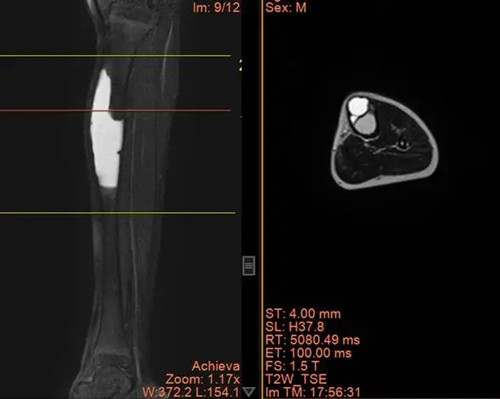

骨科三病区闫鹏主任、樊彦伟副主任,是经验丰富、医术精湛的专家,热情地接待了他们,经过详细的询问病史,仔细地查体,结合影像学及实验室检查,诊断为:左胫骨骨肿瘤(非骨化性纤维瘤/骨巨细胞瘤/纤维性骨皮质缺损/内生软骨瘤/骨囊肿?) ,考虑左胫骨非骨化性纤维瘤可能性大。

X线可见:长骨骨干处的偏心性、多房性骨质破坏区,边界清楚。

病变区多呈圆形或椭圆形,长轴与骨干平行。

周围可有轻度硬化边,无骨膜反应。

CT 能更清晰地显示骨质破坏的范围、程度和内部结构。病变区呈低密度,边缘可有硬化,内部可见分隔。

MRI 在 T1 加权像上呈低或中等信号,T2 加权像上信号多样,可呈低、中等或高信号,取决于肿瘤内的组织成分。边缘可有低信号的硬化带。

手术方案:左胫骨上段骨肿瘤切除、髓腔刮除植骨、取对侧腓骨植入缺损区,钢板内固定术